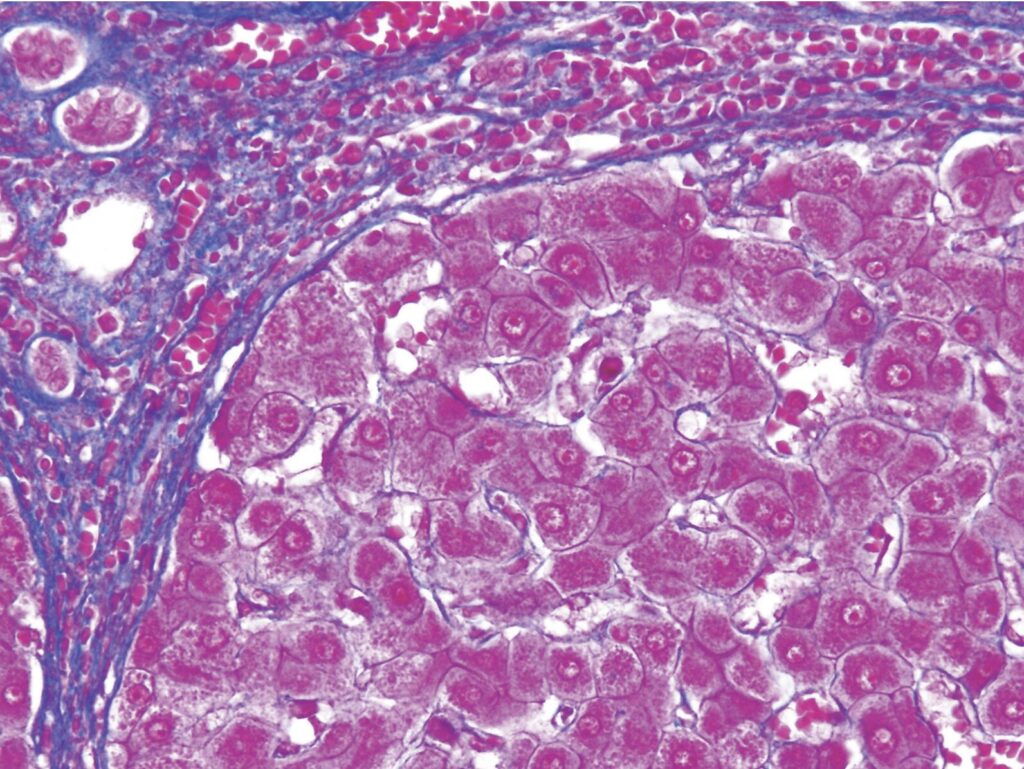

実際の画像を比較して鑑別点を理解しましょう。

次に拡大した画像も見てみましょう。

腎組織の特殊染色標本(別冊 No.6)を別に示す。

使用する染色液はどれか。2つ選べ。

1.マッソン〈Masson〉液

2.ワンギーソン〈van Gieson〉液

3.アゾカルミン G 液

4.鉄ヘマトキシリン液

5.アニリン青オレンジ G 液

問題 67A47

肝臓の特殊染色標本(別冊No.6)を別に示す。

染色はどれか。

1.azan 染色

2.oil red O 染色

3.Victoria blue 染色

4.toluidine blue 染色

5.Masson trichrome 染色